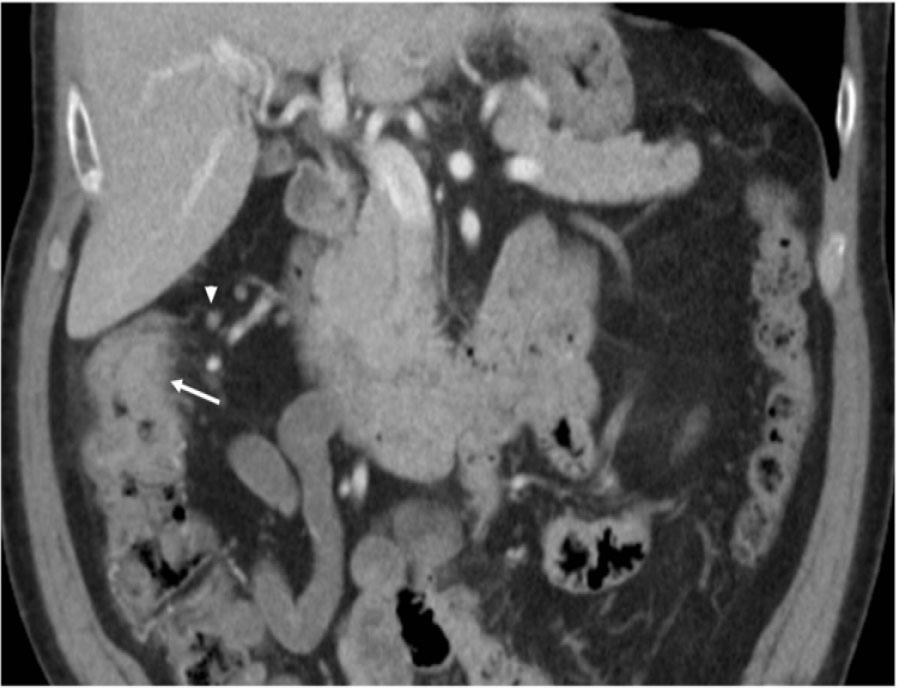

A 82-year-old Caucasian male with no significant past medical history presented to the hospital with abdominal pain, 7/10, gradual in onset for the past 2 months with last bowel movement 2 days ago. Computed tomography (CT) of the chest, abdomen, and pelvis on admission, as presented in Figure 1, showed thickening of the ascending colon concerning malignancy. He underwent colonoscopy, which showed a tumor in the ascending colon, with several adjacent enlarged lymph nodes (LNs) representing extension of the disease, with no acute findings in the chest. He later underwent right hemicolectomy, which showed poorly differentiated carcinoma, composed of sheets and cords of malignancy, abundant eosinophilic cytoplasm, and nuclei with vesicular chromatin and prominent nucleoli. There were some areas suggestive of poorly formed glands associated with brisk inflammatory infiltrate mainly composed of lymphoplasmacytic infiltrate at the base of the tumor as well as intercalating between tumor cells as described in Figures 2 and 3. Immunohistochemistry (IHC) stains showed patchy positivity for CDX2 and rare tumor cells positive for CK7 and negative for CK20, p40, synaptophysin, and chromogranin. There was loss of expression of MLH1 and PMS2. All the above features are suggestive of MC with invasion into pericolonic tissue, 0/44 LNs involved, negative margins, with no lymphovascular invasion (LVI) or perineural invasion (PNI) and deficiency in mismatch repair protein (dMMR) (loss of MLH1, PMS2 expression) noted. Final stage pT3N0 (Stage 2) was diagnosed. With the given tumor being pT3 and MSI-H, active surveillance was recommended with no adjuvant therapy. He is currently doing well with no signs of disease recurrence.

Circumferential thickening and heterogenous attenuation of the ascending colon just proximal to the level of the hepatic flexure.